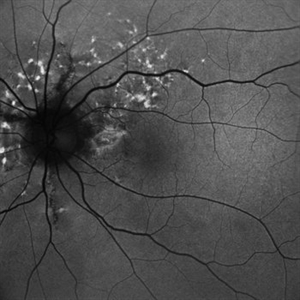

Fundus Autofluorescence Showing Angioid Streaks with Regressing CNV s/p AntiVEGF Injections (LE)

Sep 20 2024 by Anand Temkar

A 45 year old male came to our OPD with chief complaints of DOV in BE since 2 months and wavy vision in periphery. Patient was diagnosed with (BE) CNVM in a case of Angioid Streaks and has already received (BE) bevacizumab x 2.

Photographer: Dr.Anand Temkar- Retina Foundation, Ahmedabad

Imaging device: Mirante

Condition/keywords: Angioid Streaks, choroidal neovascularization (CNV), fundus autofluorescence (FAF)